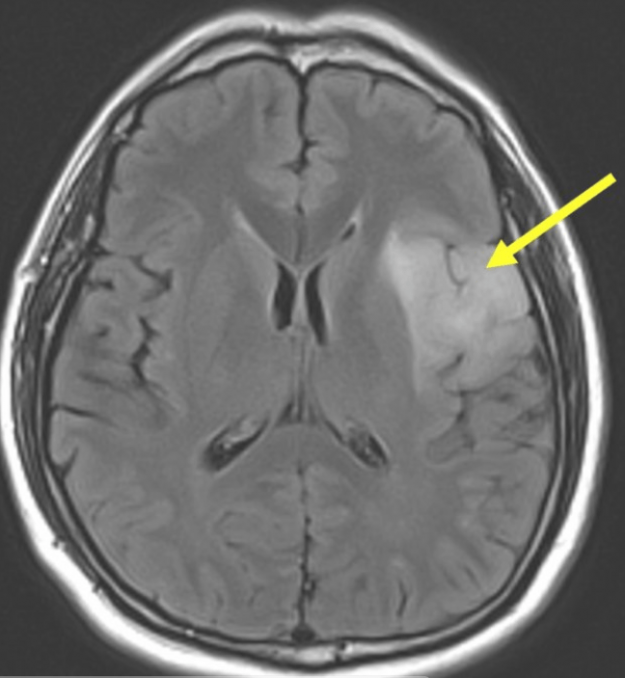

Μηνιγγίωμα: Τύποι, Συμπτώματα, Διάγνωση, Θεραπεία, Κίνδυνος Κακοήθειας και Νέες Εξελίξεις 2026